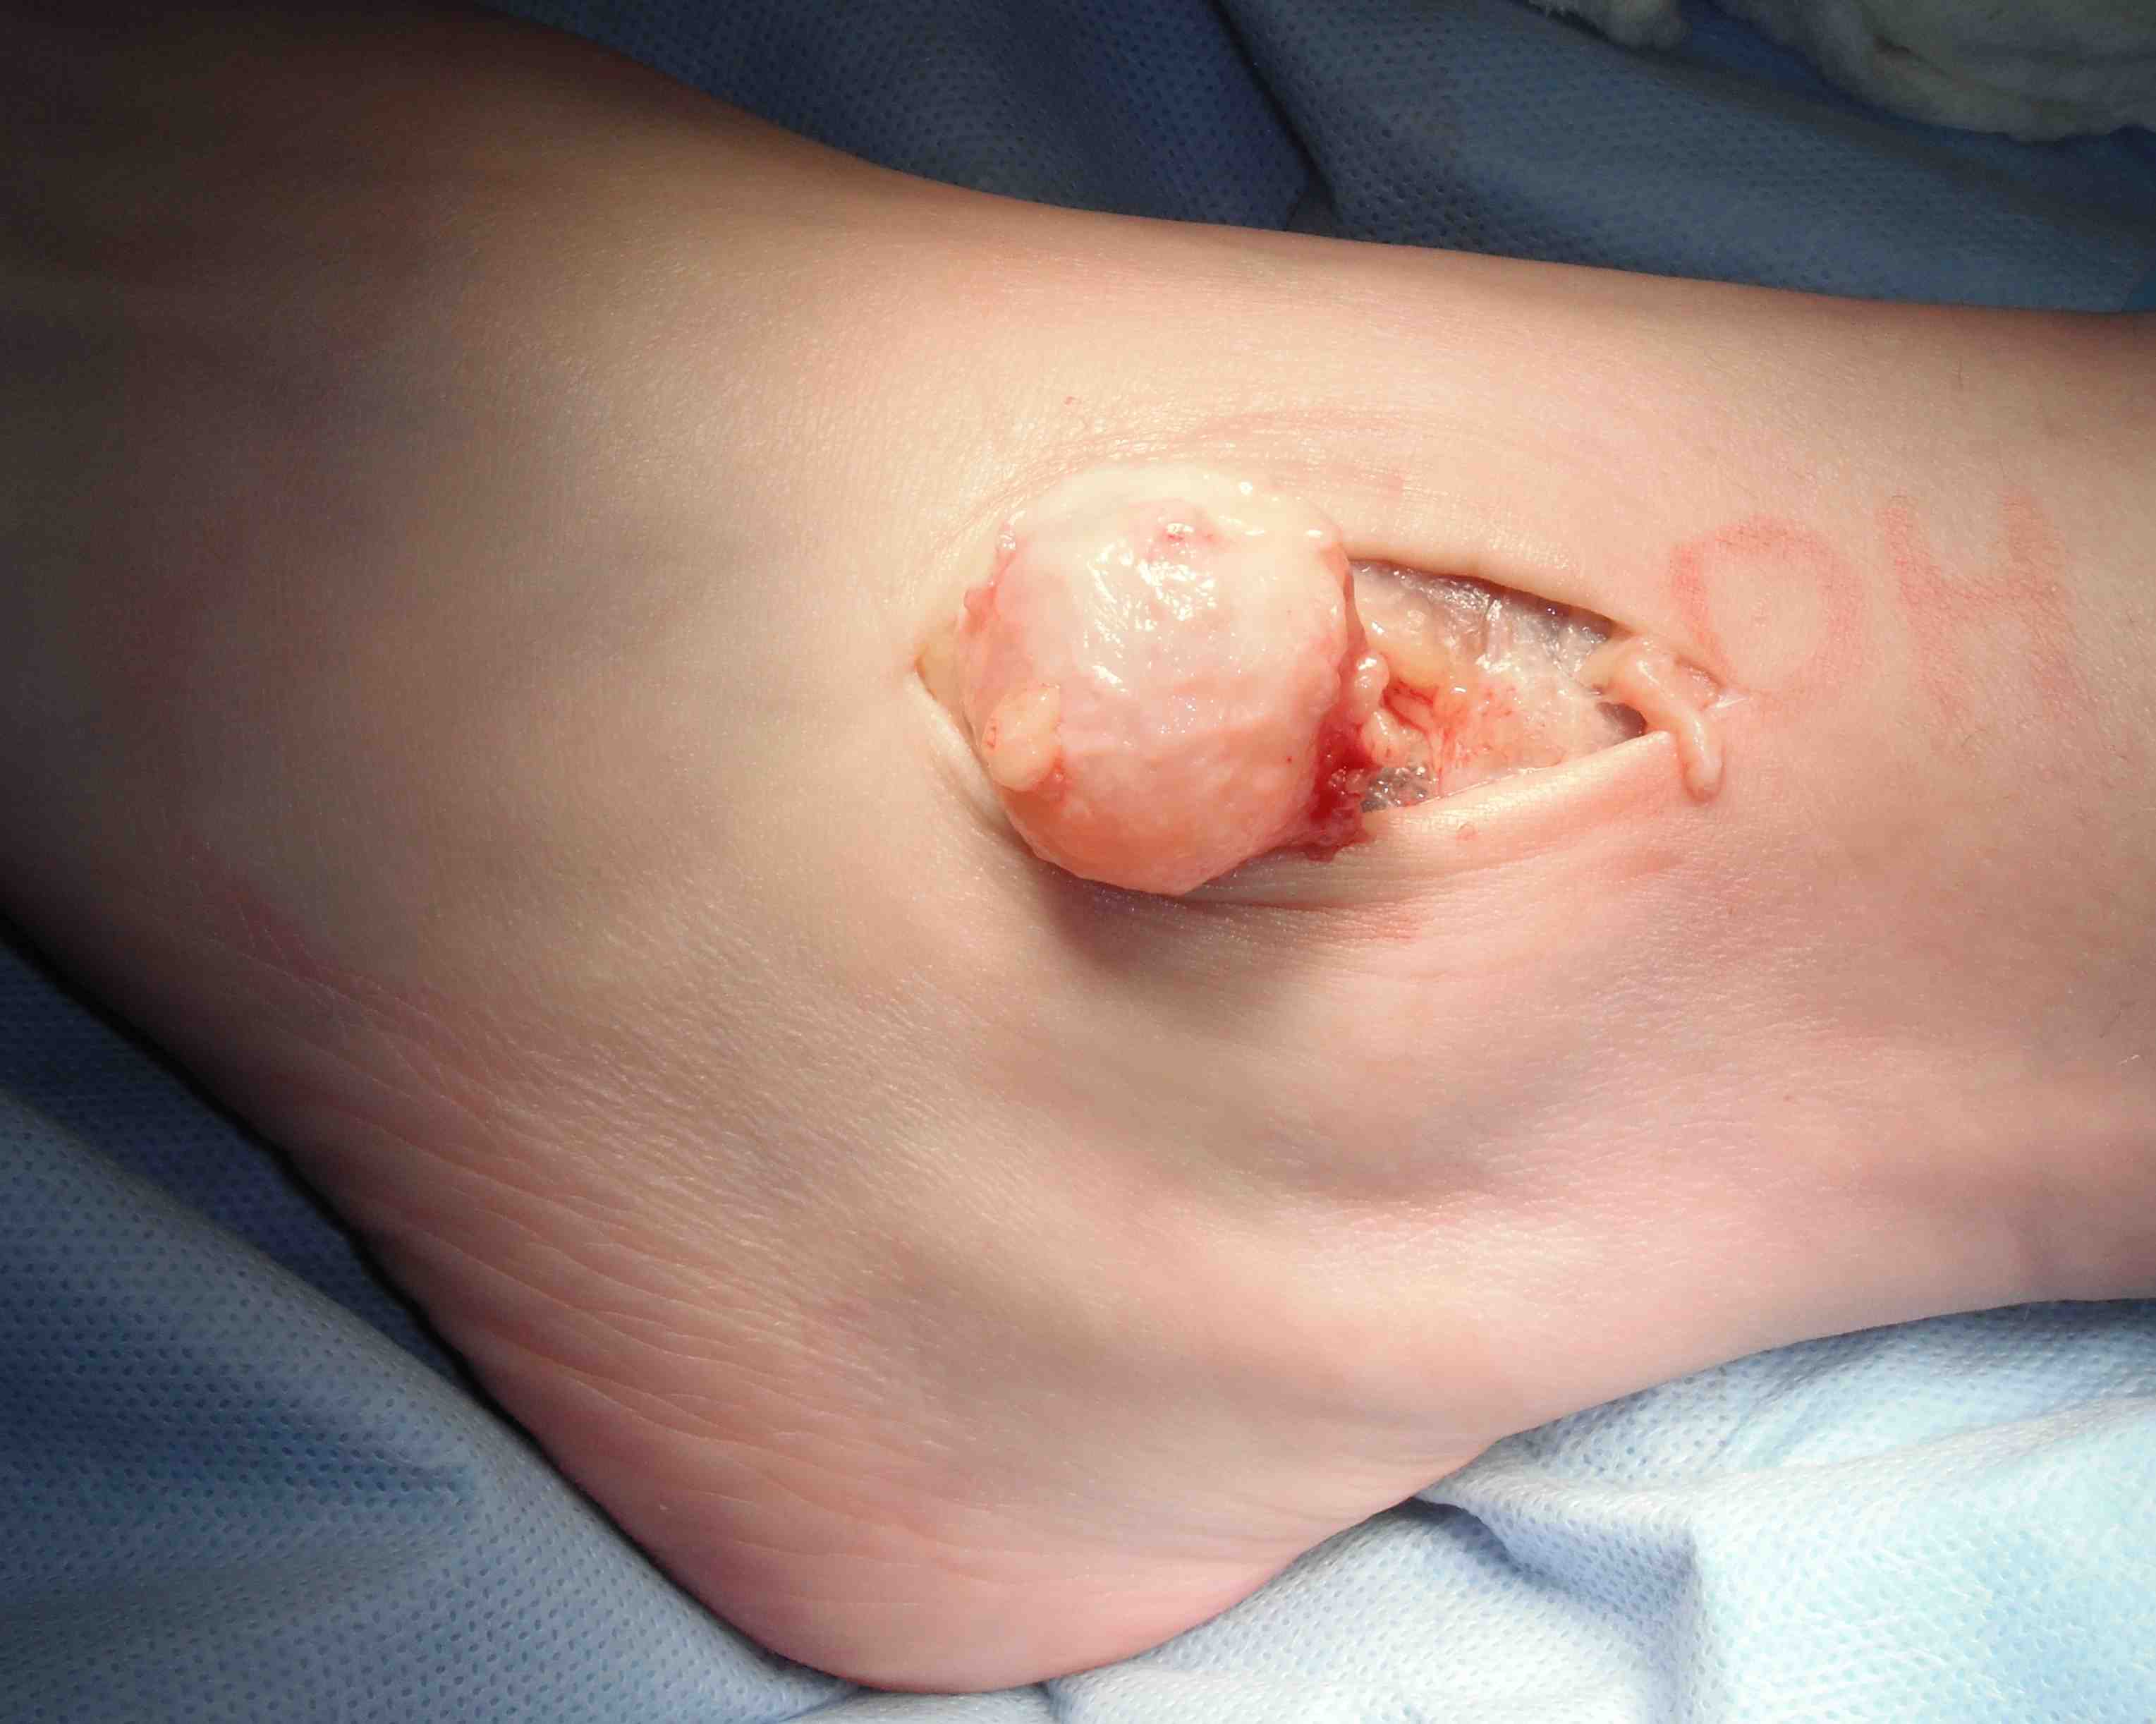

Treatment

- observe

- local excision

Zhang et al J Foot Ankle Surg 2013

- surgical excision of 20 giant cell tumour tendon sheath foot & ankle

- recurrence rate 20%